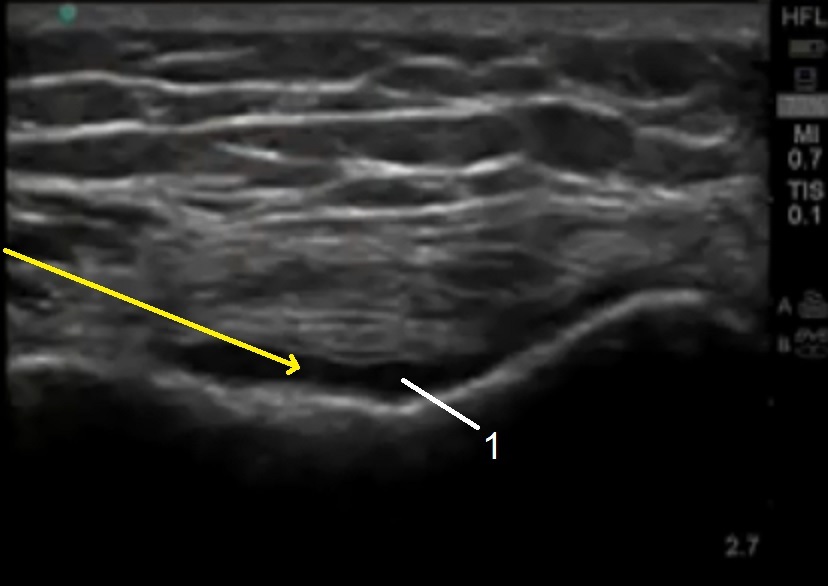

膝の解剖1の画像

黄色の矢印:これは針の経路です

膝蓋の凹部